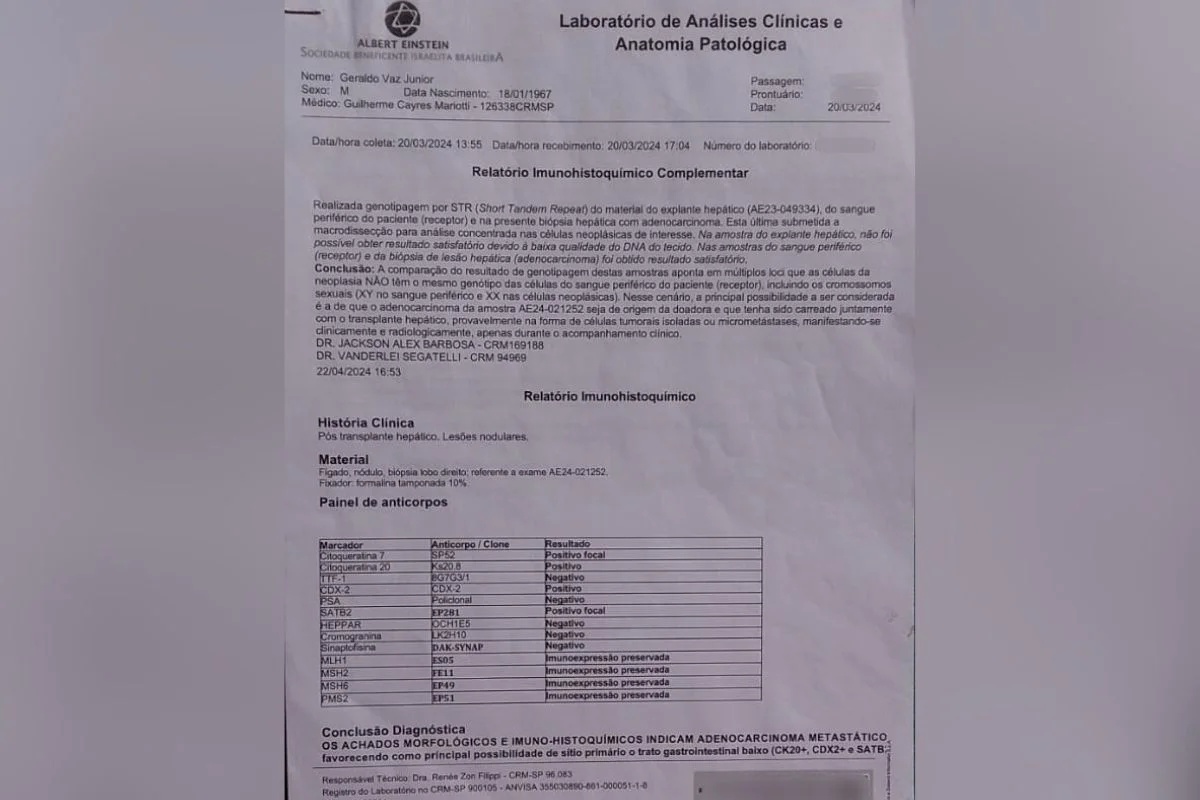

Exame de DNA feito no Hospital Albert Einstein que aponta origem do adenocarcinoma no fígado transplantado em Geraldo

Material cedido ao Metrópoles 6 de 7

Um exame de DNA, feito em março de 2024, comparou o material genético do paciente com a biópsia dos nódulos cancerígenos. O resultado apontou que “as células da neoplasia não têm o mesmo genótipo das células do sangue periférico do paciente”, concluindo, então, que o tumor teve origem no órgão transplantado.

A médica especialista em medicina legal e perícia, Caroline Ditaix, analisou os exames, cuja realização foi confirmada à reportagem, e afirmou que o resultado constitui uma prova definitiva da origem do câncer.

“Cada pessoa tem uma ‘impressão digital genética’ única. Esse exame comparou o DNA das células do câncer com o DNA do Geraldo e com o DNA da pessoa doadora do fígado. O resultado foi conclusivo: as células do tumor têm o DNA do doador, não do paciente”, explicou a médica.

O laudo hospitalar evidencia que as células cancerosas do fígado possuem cromossomos sexuais femininos (XX), enquanto Geraldo, sendo homem cis, possui cromossomos masculinos (XY). “É como se as células do tumor ‘assinassem’ que vieram de uma mulher, não dele”, comentou a especialista.